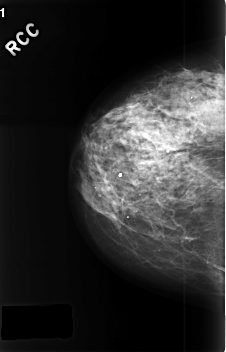

C_0379_1.RIGHT_CC

RIGHT_CC LINES 4568 PIXELS_PER_LINE 2936 BITS_PER_PIXEL 12 RESOLUTION 50 NON_OVERLAY